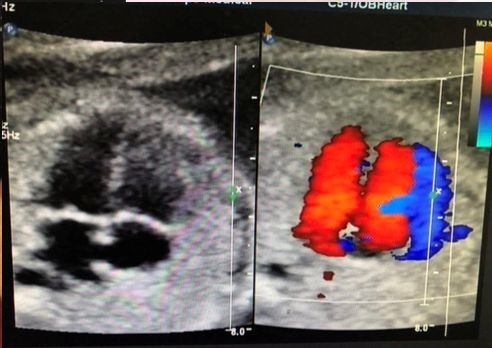

无论是“黑白B超”还是做“彩色B超”,对实质脏器扫描成像,重构出来的图像其实都是黑白的,没有截然区别。“彩色”不是把画面做成彩色,而是标示血流信号的。只有看血流显示的时候才用到彩色,就是人们看到的红色和蓝色的信号。